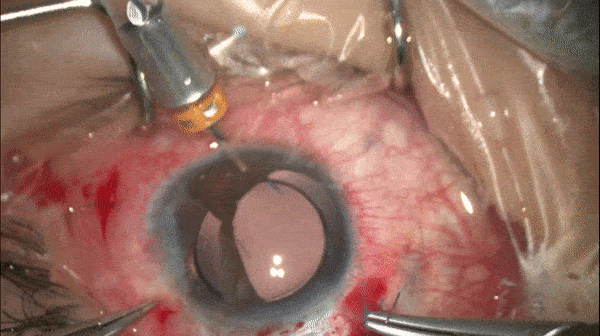

Step 10

无瓣膜巩膜缝线固定对侧攀

对侧攀重复步骤8和步骤9的操作。(图示完成后)

开睑器怎么用术说睛彩 | 金海鹰教授:使用8-0缝线的无巩膜瓣人工晶体固定手术_https://www.jmylbn.com_新闻资讯_第13张